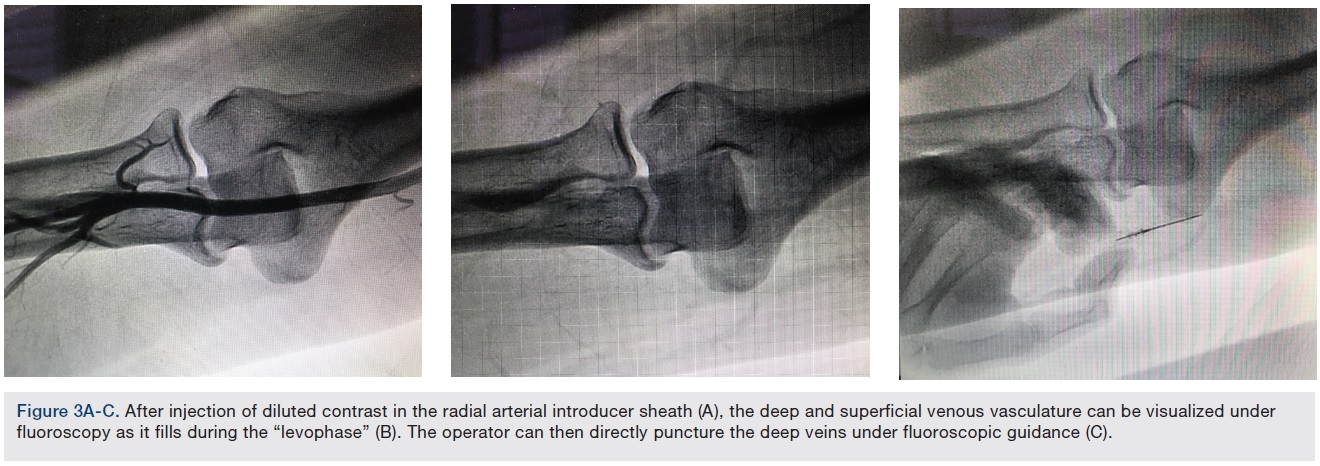

For those patients with difficult-to-access superficial veins, the operator may use adjuncts such as real-time ultrasound guidance. In patients undergoing a left and right heart catheterization, local circulatory physiology could be exploited to facilitate deep vein access, using the “Levogram technique”.4 After injection of diluted contrast in the radial arterial introducer sheath (Figure 3A), the deep and superficial venous vasculature can be visualized under fluoroscopy as it fills during the “levophase” (Figure 3B). The operator can then directly puncture the deep veins under fluoroscopic guidance (Figure 3C). This technique allows the operator to reliably puncture difficult-to-access veins without the need for additional equipment. It increases operator radiation exposure, and hence should be used if other techniques are unsuccessful or not available.